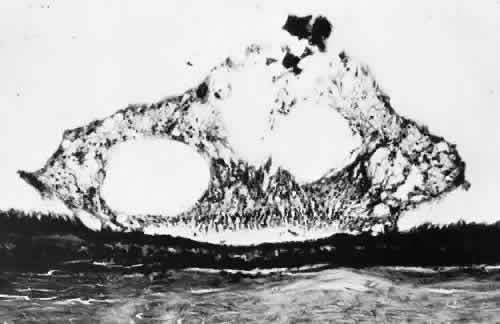

Fig. 10. Microsection of meridional complex through atypical dentate process and

its meridional fold. Anteriorly (on the left) the complex shows marked

redundancy of pigmented epithelium in its outer aspect and a dense glial

plaque on its inner aspect. Posteriorly (on the right) there is microcystoid

change, nonspecific degeneration, and dense-staining glial

cells along its surface. (Hematoxylin-eosin; × 63.) Fig. 10. Microsection of meridional complex through atypical dentate process and

its meridional fold. Anteriorly (on the left) the complex shows marked

redundancy of pigmented epithelium in its outer aspect and a dense glial

plaque on its inner aspect. Posteriorly (on the right) there is microcystoid

change, nonspecific degeneration, and dense-staining glial

cells along its surface. (Hematoxylin-eosin; × 63.)